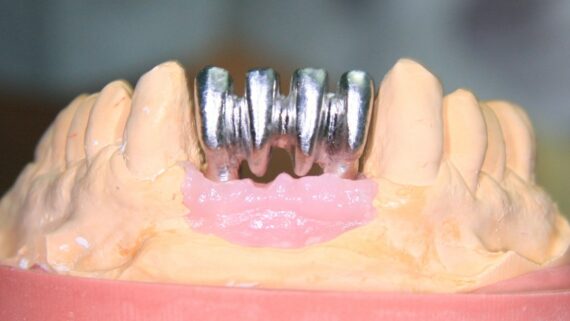

Вторым важным моментом является поиск разумных компромиссов — т. е. выбор таких вариантов лечения, которыми, возможно не будет достигнут «идеальный» (с точки зрения врача) результат, но при этом все риски будут сведены к минимуму. Например, при выраженной атрофии костной ткани по высоте мы бы разложили лечение на два этапа — сначала провели бы «наращивание костной ткани», затем -имплантацию и протезирование. Для пациентов, принимающих бисфосфонаты, подобный план лечения будет несоразмерным рискам, поэтому в их лечении мы пойдем на компромисс, будем использовать имплантаты поменьше и потоньше, в разумных пределах нарушая имплантологическое правило №2, возможно даже компенсируем атрофию «искусственной десной» — безусловно, такой вариант хирургического лечения будет для них значительно более безопасным.

Вместе с тем, у нас есть значительный позитивный опыт проведения остеопластических операций (наращивание костной ткани и синуслифтинг) у пациентов на антиостеопорозной терапии. Но это не отменяет того, что проведение таких вмешательств должно быть сведено к минимуму — вплоть до отказа в пользу других, пусть и компромиссных вариантов лечения.

Третий момент имеет значение для имплантологического лечения — это грамотное и тщательное планирование предстоящих операций, в т. ч. с использованием хирургических шаблонов.

Точные и хорошо спроектированные хирургические шаблоны для имплантации позволяют не только правильно позиционировать имплантаты, тут мы и без сопливых справляемся. Намного важнее, что их использование сокращает время хирургической операции и снижает её травматичность путем уменьшения размера операционной раны. Мы не теряем время на этап позиционирования и примерок, у нас нет необходимости в большой ране — мы можем сделать разрез точно под лунку имплантата. Конечно, такие технологии хороши и для полностью здоровых пациентов, но в случае с людьми, принимающими бисфосфонаты, их использование более, чем целесообразно.

Вторым, уже упоминавшимся нюансом является отказ от лечения по принципу «всё и сразу» даже в ситуациях, когда это возможно:

Другими словами, если в нормальных условиях мы бы объединили синуслифтинг и имплантацию в одно хирургическое вмешательство, то в случае лечения пациентов, принимающих бисфосфонаты, лучше делать всё последовательно.

Третий пункт, — и мы про это тоже говорили, — это приоритет малотравматичных, пусть и компромиссных по результату методов лечения. Например, если в тех же нормальных условиях мы будем следовать имплантологическому правилу №2, то при лечении пациентов на антиостеопорозной терапии от него можно отступить в разумных пределах: использовать имплантаты меньших длины и диаметра, установить их в компромиссное положение и т. д.